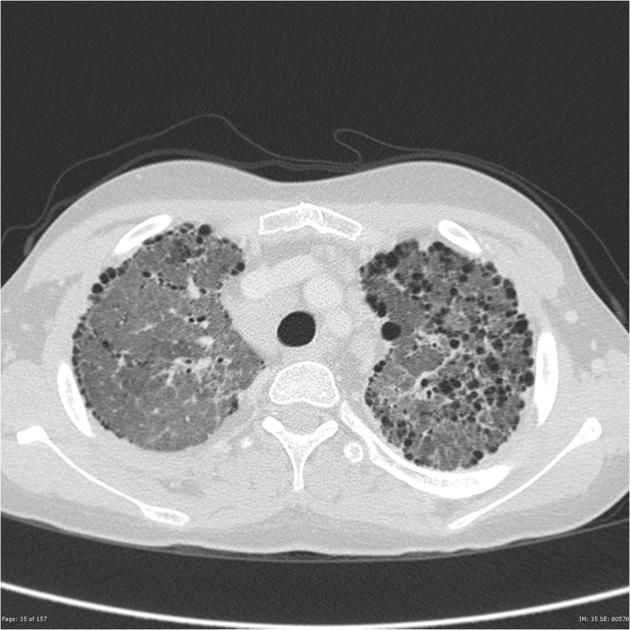

NEHI

Neuroendocrine Cell hyperplasia of Infancy

one of the peds ILDs

Central GGO, lingular and RML MC